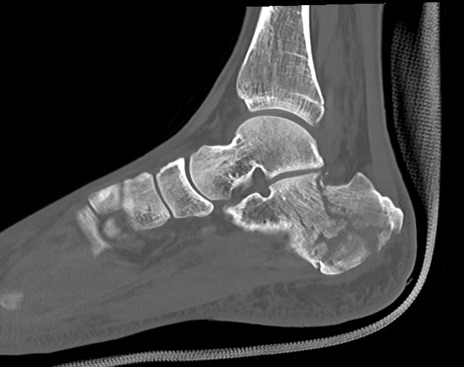

症例37 左足関節CT(矢状断像)

左足関節CT

冠状断像